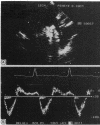

End diastolic flow velocity just beneath the aortic isthmus was measured within 72 hours of cardiac catheterisation by pulsed Doppler echocardiography in 30 controls and 61 patients with aortic regurgitation. The end diastolic flow velocity was determined at the peak R wave on a simultaneously recorded electrocardiogram. In all controls there was no reverse flow at the end diastole beneath the aortic isthmus. In patients with aortic regurgitation the end diastolic flow velocity correlated well with the angiographic grade of regurgitation (r = 0.81) and regurgitant fraction (r = 0.82). The mean (SD) values were 6.3 (5.2), 12.2 (4.3), 22.1 (5.7), and 34.3 (9.3) cm/s for patients with regurgitant fraction of less than 20%, between 20% and 40%, between 41% and 60%, and greater than 60%, respectively. An end diastolic flow velocity of greater than 18 cm/s predicted a regurgitant fraction of greater than or equal to 40% with a sensitivity of 88.5% and a specificity of 96%. The study suggests that the pulsed Doppler derived end diastolic flow velocity is a useful index in the routine non-invasive assessment of the severity of aortic regurgitation.